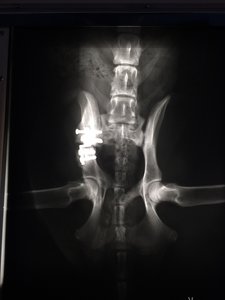

Ich hab mir mal die Röntgenbilder schicken lassen.

Hier sieht man mal den Spalt der nach dem Sturz entstanden war man sieht auch, wie sehr der Beckenknochen in Richtung Wirbelsäule gedrückt wurde :shock:

Hier mal im direkten Vergleich: direkt nach der OP

So sieht es jetzt aus. Knochenmaterial noch etwas "dünn", aber jetzt schon soweit, dass sie absolut nicht mehr humpelt oder hoppelt und auch wieder komplett belastet.

Ich find's halt so krass, wie weit nach innen sich das Becken verschoben hat :shock:

Aber der Chirurg meinte, dass es kein Problem darstellt, so lange sie nicht trächtig wird, aber das Thema hat sich ja eh erledigt...